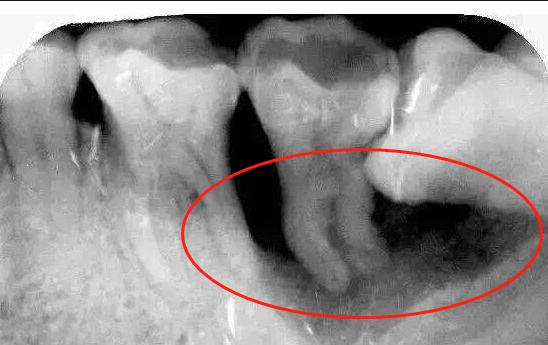

3、 牙齿龋坏

牙齿龋坏的时候没有及时进行修复,导致后续腐烂程度加深,影响牙根神经,造成整牙冠以及牙根全都烂没了。